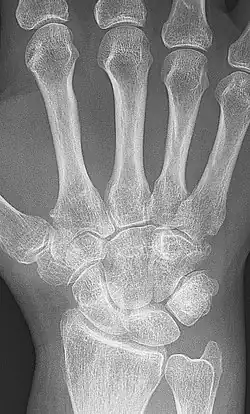

Ankylosis (from Greek ἀγκύλος (ankulos) 'bent, crooked') is a stiffness of a joint due to abnormal adhesion and rigidity of the bones of the joint, which may be the result of injury or disease. The rigidity may be complete or partial and may be due to inflammation of the tendinous or muscular structures outside the joint or of the tissues of the joint itself.[1]

When the structures outside the joint are affected, the term "false ankylosis" has been used in contradistinction to "true ankylosis", in which the disease is within the joint. When inflammation has caused the joint-ends of the bones to be fused together, the ankylosis is termed osseous or complete and is an instance of synostosis. Excision of a completely ankylotic shoulder or elbow may restore free mobility and usefulness to the limb. "Ankylosis" is also used as an anatomical term, bones being said to ankylose (or anchylose) when, from being originally distinct, they coalesce, or become so joined that no motion can take place between them.[1]